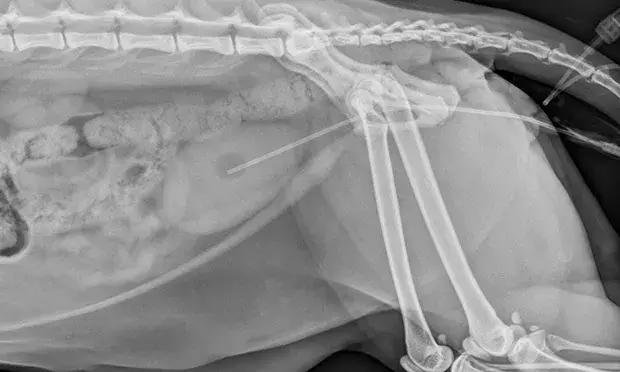

一旦发现尿道阻塞,就需要紧急治疗。通常建议进行血液学检查(血常规、血液生化)和尿液检查,来帮助寻找尿道阻塞的原因,而X线和B超能帮我们判断是否有尿结石或尿结晶。

最重要的是,必须尽快使尿道恢复通畅。由于疼痛以及喵星人胆小易受惊的性格,我们可能需要给猫咪打镇静剂或者进行全身麻醉,再从排尿口插入导尿管,利用水流将堵塞物冲回膀胱。

(这张X线片中的长条状物就是导尿管)